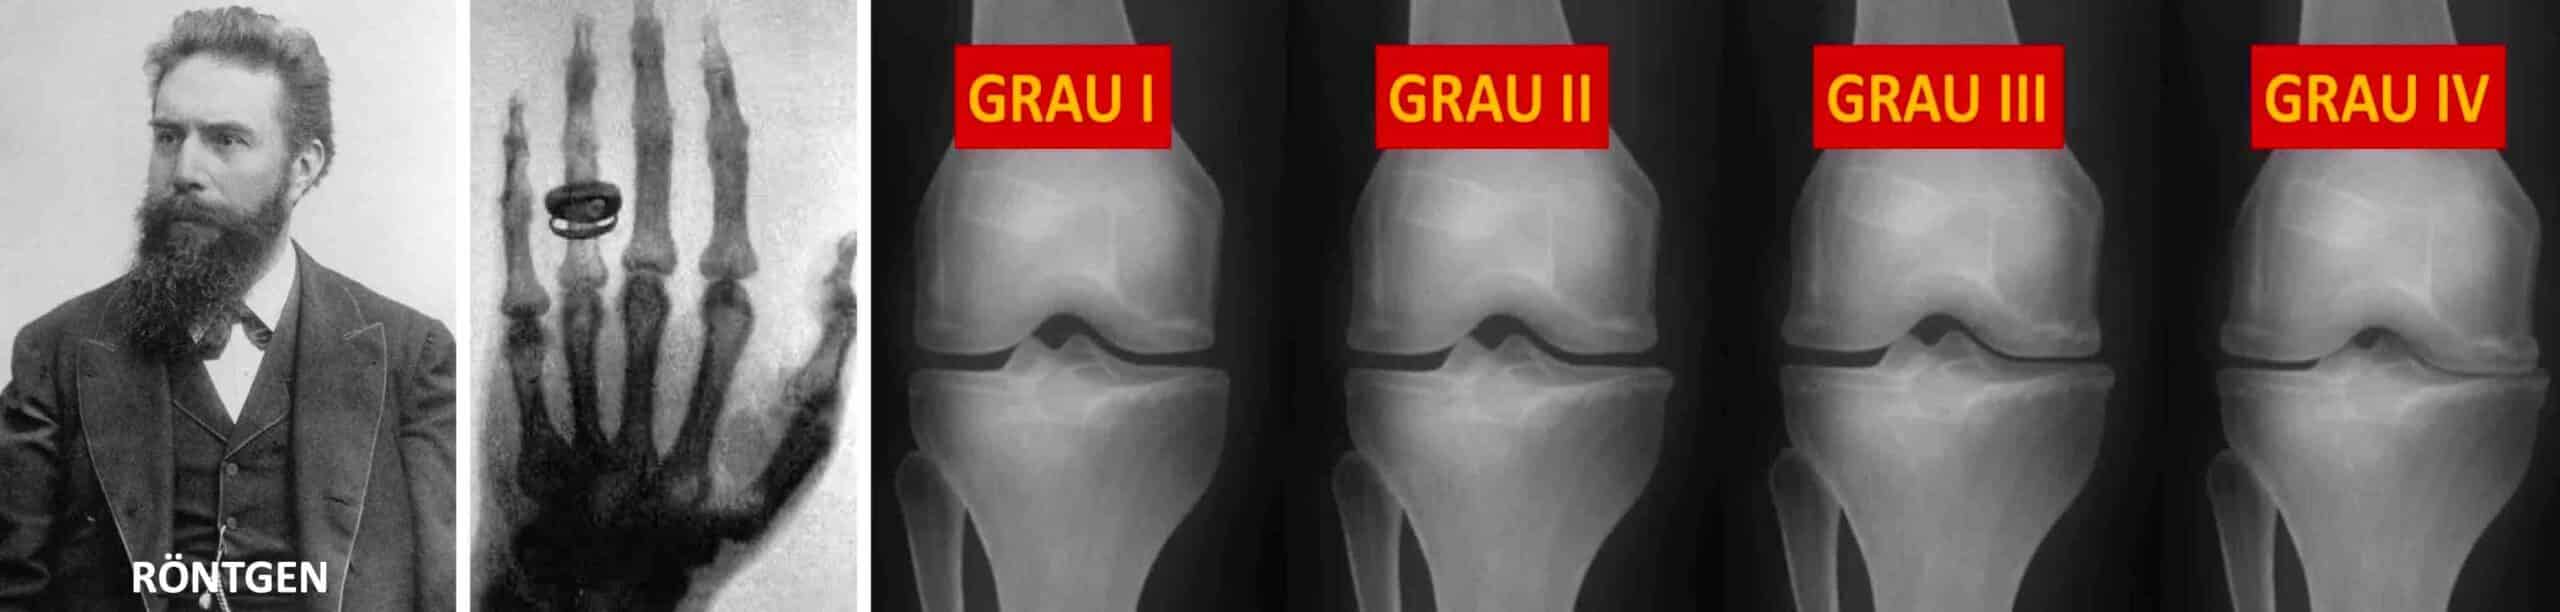

O século XX foi marcado por vários avanços diagnósticos e clínicos para a artrose do joelho. Primeiro foi a radiologia. A invenção dos raios X ( 1.895 ) foi um marco fundamental. A partir de então tornou-se possível visualizar os sinais de desgaste da cartilagem e os osteófitos, estabelecendo o diagnóstico da artrose do joelho com mais precisão. Durante o século XX surgiram sistemas de classificação da artrose do joelho baseados em sintomas e achados radiológicos, como a classificação de Kellgren-Lawrence de 1.957. Em relação aos tratamentos, foi nessa época que surgiram as terapias conservadoras com fisioterapia, anti-inflamatórios, infiltrações articulares e, mais recentemente, o desenvolvimento das próteses de joelho para substituição dos joelhos gravemente acometidos pela artrose. Os implantes das próteses de joelho continuam sendo aperfeiçoados até os dias de hoje. Em 1.987, no Japão, foi aprovado o primeiro medicamento à base de ácido hialurônico para uso intra-articular no joelho.